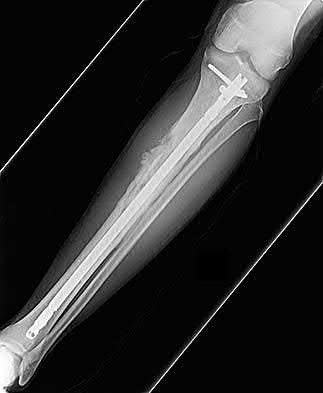

Recombinant human Bone Morphogenetic Protein-2 (rhBMP-2) is FDA approved for use in acute, open tibial shaft fractures stabilized with an intramedullary nail. rhBMP-7 (Osteogenic Protein-1 or OP-1) previously had a Humanitarian Device Exemption (HDE) for recalcitrant long bone nonunions but is no longer commercially available in the US for this indication.